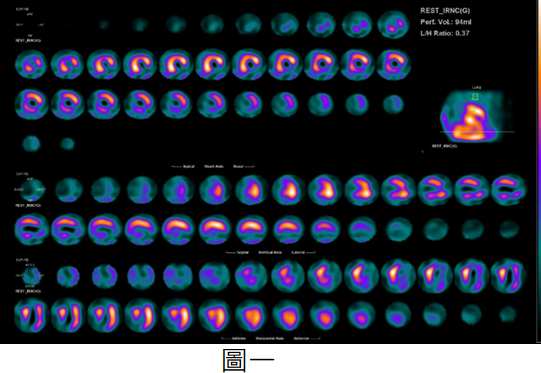

【111-2 醫學(三) 第9題】59 歲男性,過去有冠狀動脈疾病開過繞道手術,最近 6 個月運動時胸悶加劇、喘,就診時發現心電圖有新的變化,因此心臟科醫師安排了靜態核醫心肌灌流單光子造影(MPI-SPECT)(圖一)及 F-18 FDG 正子掃描(PET)(圖二),下列敘述何者錯誤?

心臟血管內科26 / 76